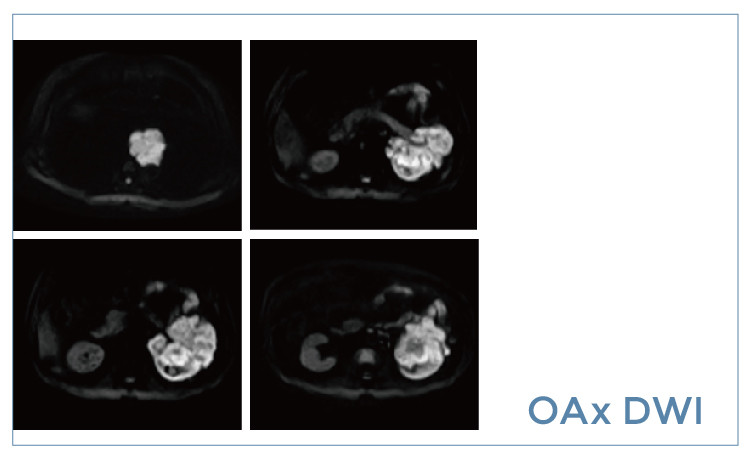

【朗润影像档案】20190426磁共振影像病例结果讨论